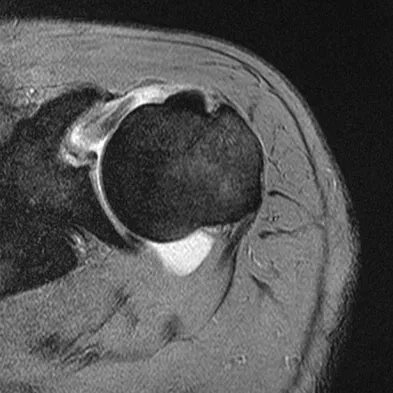

A patient has right shoulder pain. Figure 1a shows a gadolinium-enhanced transverse MRI scan at the level of the coracoid. Figure 1b shows an arthroscopic view of the anterior structures from a posterior portal. These images reveal which of the following findings?